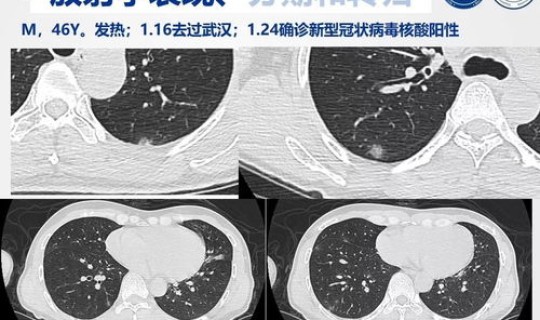

一、我市新增1例输入性新型冠状病毒感染的肺炎确诊病例 1月22日18时许,四川省卫生健康委发布消息,我市新增1例输入性新型冠状病...